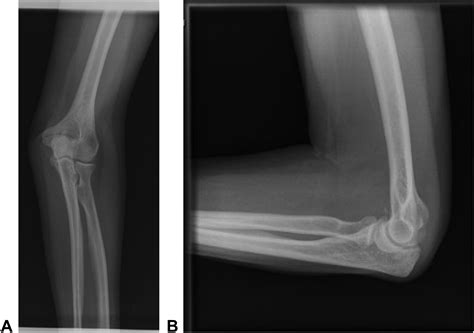

Diagnosing radial head subluxation typically involves a physical examination by a healthcare provider. The diagnosis is usually based on the child's history and the characteristic symptoms. In some cases, an X-ray may be ordered to rule out other potential injuries, such as fractures. However, X-rays are not always necessary for diagnosing radial head subluxation, as the condition is primarily clinical.

Elbow Anatomy

• radial head subluxation x ray